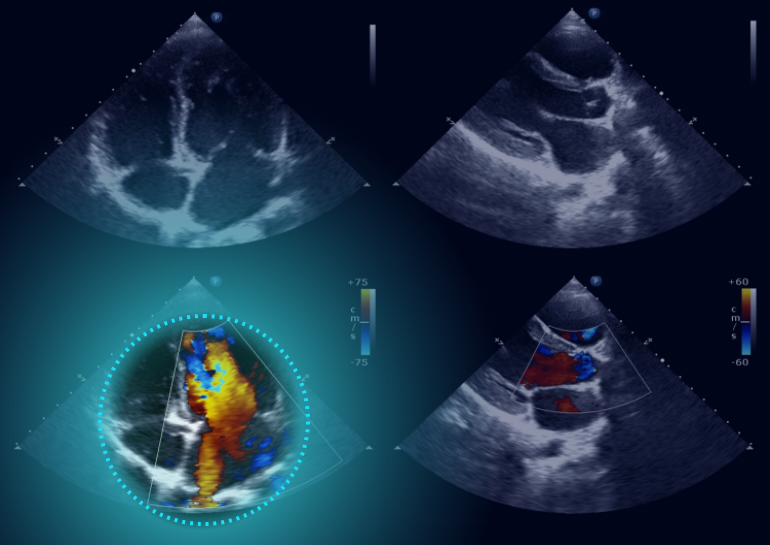

Automated Cardiac Image Analysis and Interpretation

Dyad Medical Inc. |